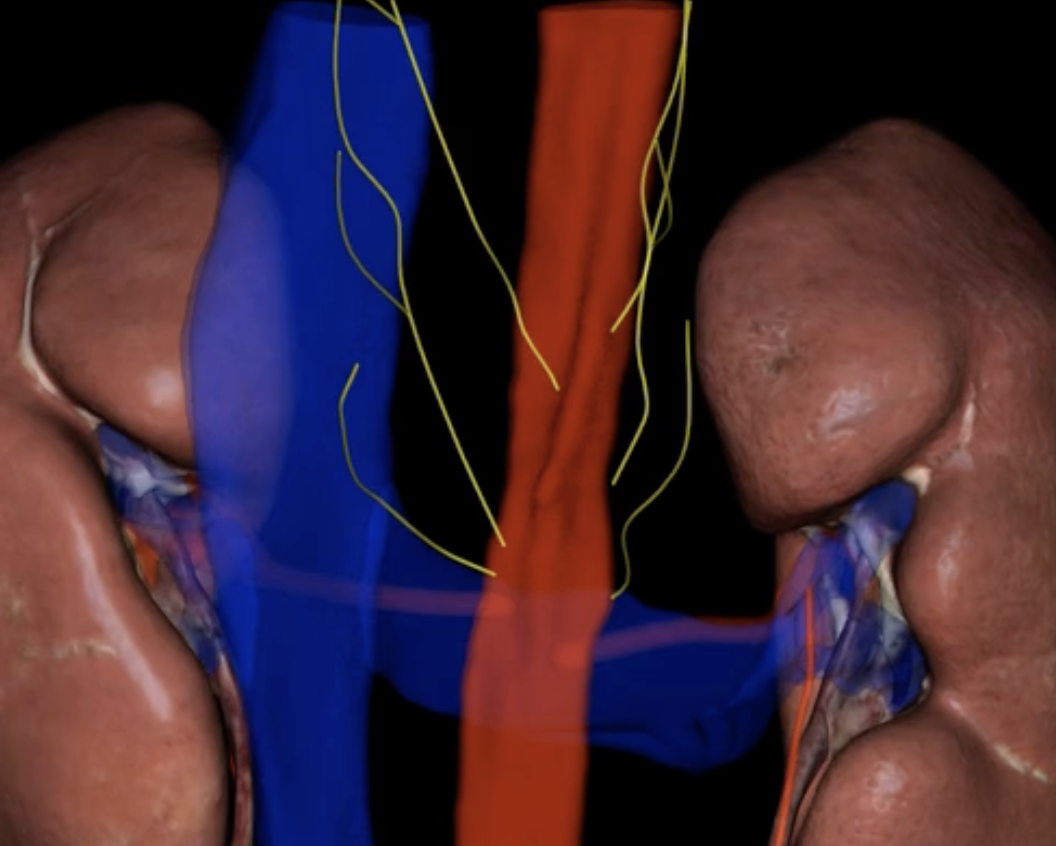

green: renal hilum

yellow: ureter

red: abdominal aorta

green yellow and red

renal plexus

the kidneys are innervated by sympathetic and parasympathetic nervous system via

sympathetic nerve fibers from T10-T12/ splanchnic nerves

role in blood pressure regulation

yellow

Vagus nerve

the parasympathetic innervation occurs thru the